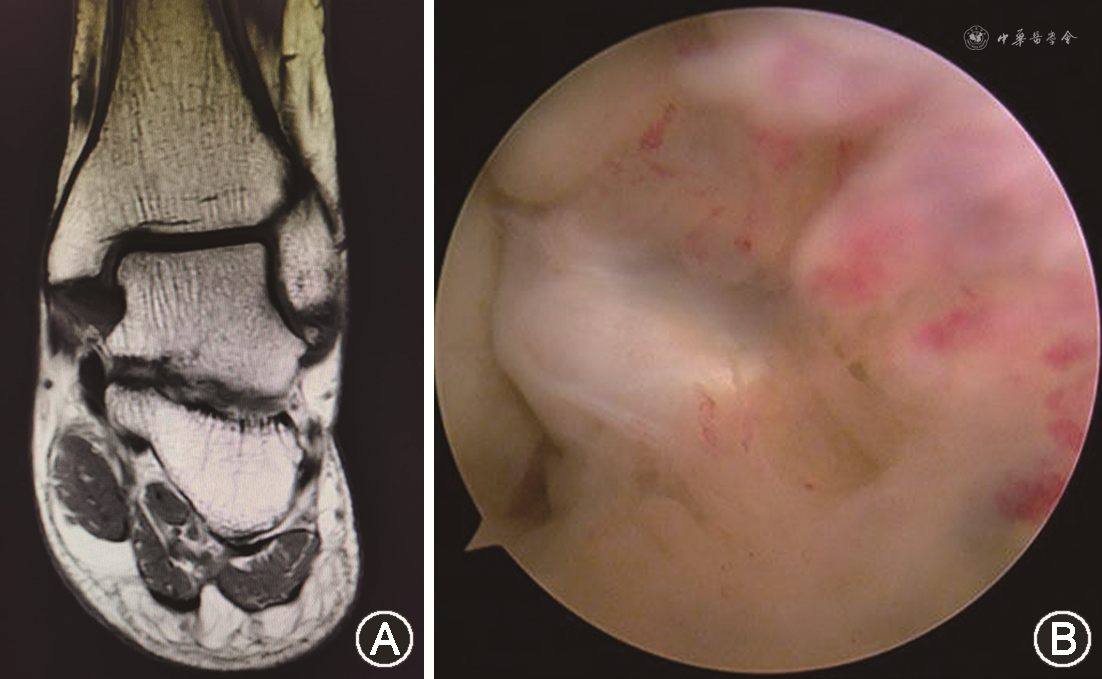

术前比较双侧踝关节应力位X线片,可见踝关节稳定性可(图1A、B、C、D),双下肢力线良好(图1E),踝关节CT及MRI检查显示SFO的存在,并与周围韧带组织相连(图1F~I),术前测量SFO最长径为(4.1±1.4)mm,其中9例(60.0%)<5 mm,6例(40%)为5~10 mm;所有病例SFO均完全取出(图2),术后复查踝关节CT可见SFO完全消失(图1I)。患者术中见SFO均包裹或附着于距腓前韧带,周围伴有滑膜组织和瘢痕组织增生(图3)。

通过术前影像学分析及疗效评估SFO的MRI表现,许多研究者并未发现SFO中有韧带穿过[10]。本实验中,患者的术前MRI及CT显示SFO与周围韧带组织有不同程度的相连,术中关节镜下观察到SFO均与韧带存在一定关系,或完全包裹于韧带组织中,或与韧带组织相连,这一结果与法国学者Moukoko等[11]所观察到的一致,说明通过术前影像学检查判断SFO与韧带组织之间的关系是可靠的,所以笔者认为术前影像学检查是必要的,尤其是踝关节MRI检查,能较为直观的显示SFO与周围的韧带组织关系,有利于评估其大小、位置和解剖关系,进而制定手术方案。